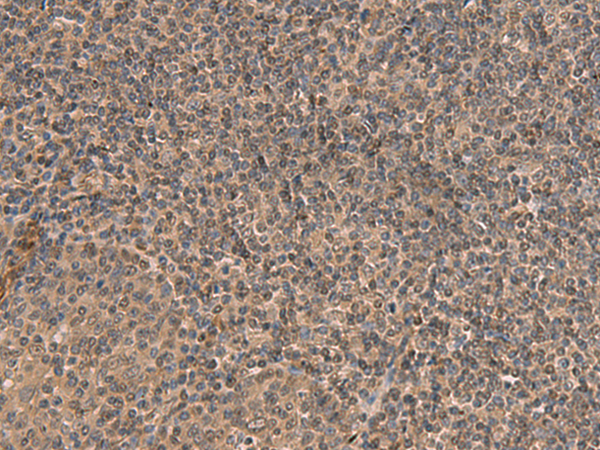

分类: 科研抗体货号: P10048别名: PP23; SOUL; C6orf34; C6ORF34B应用: IHC反应种属: Human, Mouse